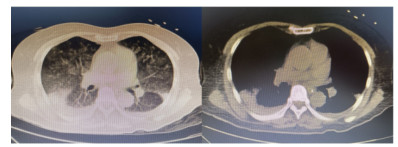

患者,女,64岁,居住农村,既往有糖耐量异常5年,未正规治疗,4年前诊断为“原发性甲状腺功能亢进”,经治疗已好转。无高风险、中风险地区旅居史,无境外旅居史,无新冠病毒肺炎确诊或疑似患者接触史。2020年7月31日患者无明显诱因下在家中出现发热,体温最高39.4 ℃,伴畏寒、全身乏力,无胸闷、胸痛,无咳嗽、咳痰,无腹痛、腹泻,无黑矇、晕厥,遂在家中自服“退热药”后体温降至正常,但体温仍有反复。8月2日早晨患者再次出现发热,伴畏寒、寒战,遂至本院发热门诊就诊,予查C-反应蛋白156 mg/L,降钙素原0.64 ng/L,考虑感染性发热,遂予“哌拉西林他唑巴坦钠4.5 g每12 h一次”静滴抗感染治疗,后患者突发呼吸费力,伴咳嗽、咯血,为鲜红色血液,量较多,遂于8月2日14:18送达本院急诊抢救室。来时患者呼吸急促,有咳嗽伴咳血性痰,双侧小腿持续性钝痛,查体:血压188/86 mmHg(1 mmHg=0.133 kPa),心率168次/min,呼吸36次/min,血氧饱和度50%,体温38.6 ℃。神志清,精神软,急性面容,双侧结膜略充血,全身皮肤黏膜未见明显充血、淤血,未触及淋巴结肿大。口唇微绀,两肺呼吸音粗,可闻及明显湿性啰音,心律齐,无明显病理性杂音;腹平软,无压痛反跳痛,四肢肌力Ⅴ级,两侧病理征未引出。予心电监护、特级护理、面罩吸氧、建立静脉通道,送检血常规、生化、血气、心肌酶、凝血酶原时间系列、痰培养等常规检查,同时予送检血标本行高通量测序,完善胸部CT检查(图 1)。辅助检查结果如下:8月2日胸腹部CT示两肺感染,腹部未见明显异常。血常规:白细胞计数7.9×109/L,中性粒细胞百分比89%,血红蛋白121 g/L,血小板计数104×109/L,C-反应蛋白156.82 mg/L。血生化:丙氨酸氨基转移酶51 U/L,天门冬氨酸氨基转移酶63 U/L,白蛋白34.5 g/L,总胆红素17.4 mmol/L,肌酐74 mol/L。心肌酶谱:心肌肌钙蛋白I 0.014 ng/mL,肌红蛋白322 ng/mL,肌酸激酶同工酶3.2 ng/mL。血气分析:pH 7.435,二氧化碳分压29 mmHg,氧分压53.5 mmHg,K+ 2.6 mmol/L,Na+ 132 mmol/L,血乳酸3.1 mmol/L。新型冠状病毒抗体、核酸阴性。接诊医师初步诊断为“咯血待查:疑似肺部感染,呼吸衰竭”,治疗上予亚胺培南0.5 g静滴经验性抗感染、甲泼尼龙80 mg静滴抗炎,同时予化痰、平喘等对症、支持。17:00患者出现呼吸费力加重,10 L/min面罩吸氧下血氧饱和度仍为70%,故予紧急气管插管、机械通气,随后转入ICU,联系感染科医师会诊,结合患者病史及CT影像学表现的广泛、片状密度增高影特点,考虑钩端螺旋体病可能性大,不排除“赫氏反应”,故继续予亚胺培南0.5 g静滴每6 h一次抗感染、甲泼尼龙80 mg静滴每12 h一次抗炎、白蛋白营养支持等治疗。8月3日更改甲泼尼龙80 mg静滴每天一次。8月4日高通基因测序回报:检测出问号钩端螺旋体DNA,符合入院时推断,明确病原体后予修正诊断为肺出血型钩体病伴赫氏反应。8月5日停亚胺培南,改青霉素160万单位静滴每8 h一次。8月8日患者病情稳定,拔除气管导管,予甲泼尼龙减量为40 mg静滴1次/d,8月9日复查胸部CT提示两肺斑片状、片状密度增高影较前有所吸收(图 2),停用甲泼尼龙。8月10日转入呼吸科。8月17日复查胸部CT提示两肺斑片状、片状、条索状密度增高影,较前明显吸收(图 3)。8月20日患者好转出院。9月18日随访,复查CT提示两肺散在条索状密度增高影,基本恢复正常(图 4)。

图 3 8月17日胸部CT示两肺斑片状、片状、条索状密度增高影,较前明显吸收